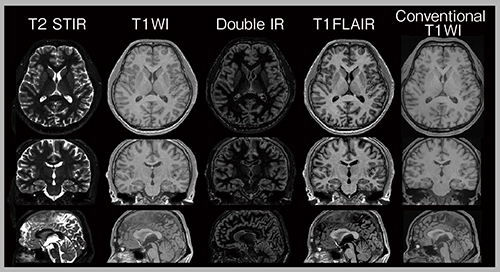

われわれは,GEとの共同研究により3D MAGiCの開発を行った。スライス方向にも高分解能が得られるため,脳形態情報のより正確な値が算出可能となる3),4)。また,3D MAGiCにパラレルイメージングと圧縮センシングを併用して撮像の高速化にも取り組んでいる5)。さらに,3D MAGiCでは,多彩なコントラスト強調画像のすべての断面を一度に取得可能となった(図2)。

図2 3D MAGiC